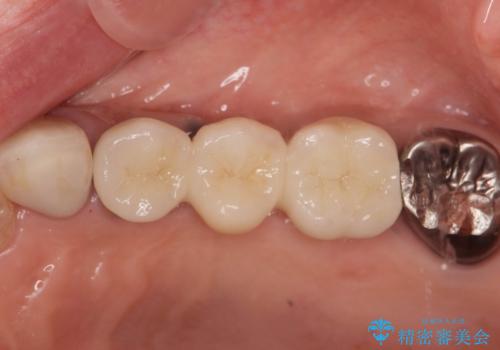

複数の奥歯の欠損 インプラントによる咬合機能回復

- 105.6万円(インプラント×2・チタンカスタムアバットメント×2・ジルコニアクラウン×3・仮歯×3)費用は治療当時の料金となります

しっかりと咬合機能の回復がなされ、また食事を楽しんでいただけるようになりました。